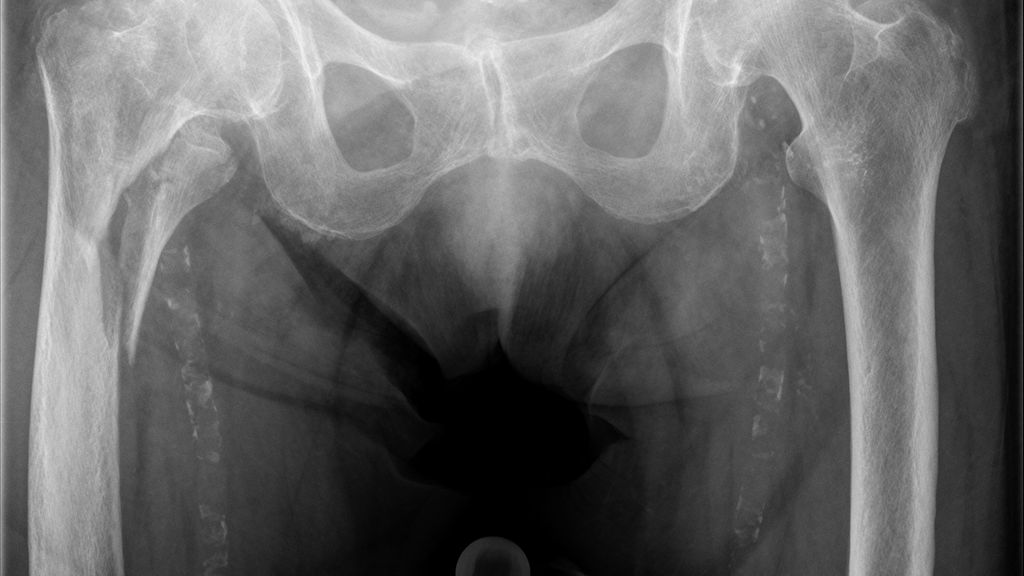

Ein erhöhtes interprothetisches Frakturrisiko besteht zwischen eingebrachten schaftgeführten Gelenkprothesen, wobei die Distanz der Schaftspitzen kleiner als 110mm ist. Zu kleine interprothetische Abstände sind Thema biomechanischer Forschung. Angenommen wird, dass zu kurze Abstände Sollbruchstellen darstellen könnten. Erhardt und Mitarbeiter beschrieben 2010, dass Abstände weniger als 6cm oder weniger als zwei Diaphysendurchmesser zu vermeiden sind. Weiterführende Studien von Weiser und Mitarbeiter zeigten 2014, dass der interprothetische Abstand keine Rolle bei der Entstehung interprothetischer Frakturen spielt, sondern dass die kortikale Dicke im Bereich der Prothesenspitzen den entscheidenden Parameter darstellt. Obwohl biomechanisch nicht bestätigt ist, wie weit die Platte die Prothesenenden überragen soll, empfehlen wir eine Schutzosteosynthese, um eventuelle zukünftige Sollbruchstellen zwischen den Prothesenenden zu vermeiden (Abb.1).

Abb. 1: 92-jährige Frau mit einer instabilen pertrochantären proximalen Oberschenkelfraktur bei liegender schaftgeführter Knieprothese. A) Das ap. Röntgen zeigt die pertrochantäre Oberschenkelfraktur. B) Um eine Sollbruchstelle zwischen dem Nagelende proximal und dem Prothesenende distal zu vermeiden, wurde eine Schutzosteosynthese mittels Platte durchgeführt